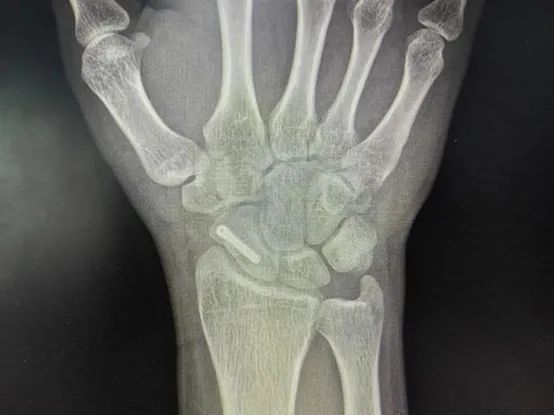

5、术后X片见内固定螺钉位置非常满意